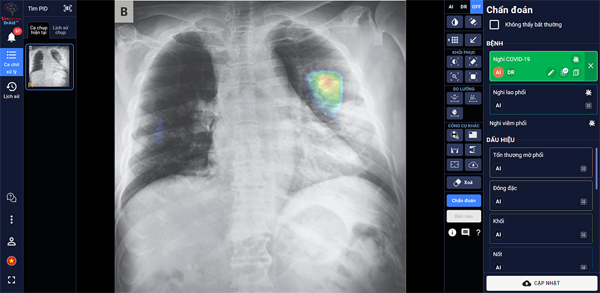

Đặc biệt, DrAid™ mang lại 4 giá trị ưu việt trong phát hiện và điều trị Covid-19 dựa trên ảnh X- quang ngực thẳng gồm: Phát hiện nhanh các dấu hiệu bất thường trong vòng chưa đầy 5 giây; Kết hợp cùng xét nghiệm PCR từ đó nâng cao độ chính xác, giảm thiểu tình trạng âm tính giả; Hỗ trợ đánh giá tiên lượng tình trạng bệnh nhân thông qua lịch sử hình ảnh chụp X-quang, để từ đó có hướng điều trị phù hợp; Hỗ trợ tăng tính nhất quán và chuyển giao kiến thức của bác sĩ từ tuyến Trung ương tới cơ sở.

![]() |

| DrAid™ hỗ trợ đánh giá tiên lượng bệnh nhân Covid-19 dựa trên hình ảnh X-quang ngực thẳng |